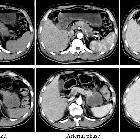

acinar-neuroendocrine carcinoma of the pancreas with positive for microsatellite instability: a case report and review of the literature. Preoperative contrast-enhanced computed tomography. The tumor was close to the celiac artery (CA), superior mesenteric artery (SMA) and vein (SMV), and common hepatic artery (CHA, A–D) The splenic artery was patent despite circumferential involvement by the tumor (A–C)

A mixed

adenoneuroendocrine carcinoma of the pancreas: a case report. Abdominal contrast-enhanced computed tomography (CT) showed diffuse enlargement of the pancreas with increased CT level in the peri-pancreatic fatty tissue and revealed a mass of 2 cm in size in the pancreas head (c–d, arrow). The mass was poorly enhanced in the arterial phase and was gradually enhanced in the venous phase. The portal vein showed narrowing (b–f, arrowhead)